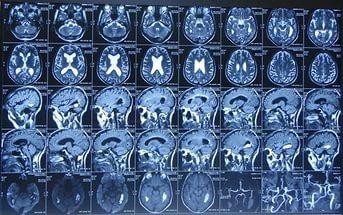

Чтение нативных снимков МРТ головного мозга больного человека, выполненных на аппаратах с мощностью магнитного поля свыше 1 Тесла, имеет высокую специфичность и достоверность. Квалифицированный врач лучевой диагностики на томограммах выявляет самые мельчайшие патологические сигналы.

Как выглядит снимок МРТ головного мозга

Без медицинского образования нельзя определить тонкости МР-изображений. Врач дифференцирует не только нормальные анатомические образования, но и определяет мельчайшие патологические тени диаметром несколько миллиметров.

Для наглядности приведем пример описания МРТ головного мозга при злокачественном новообразовании:

- Симптом «плюс ткань» – появление дополнительной тени, не являющейся анатомической структурой;

- Выявление «эффекта массы» – новообразование при росте раздвигает здоровые ткани в сторону;

- Дифференцировка между злокачественными и доброкачественными опухолями основана на изучении границ, состояния окружающих структур. Раки инфильтрируют перифокальные ткани, не имеют четких границ, быстро прогрессируют. Доброкачественные очаги отделены капсулой, формирующий четкий МР-сигнал;

- Контрастное исследование указывает на повышенное накопление веществ в густой сосудистой сети образования;

- Сигнал от опухолевого узла измененный (при сравнении с нормальной мозговой паренхимой) – темный или светлый (в зависимости от строения новообразования).

Существуют и другие признаки опухоли на томограммах, выявляемые специалистами.